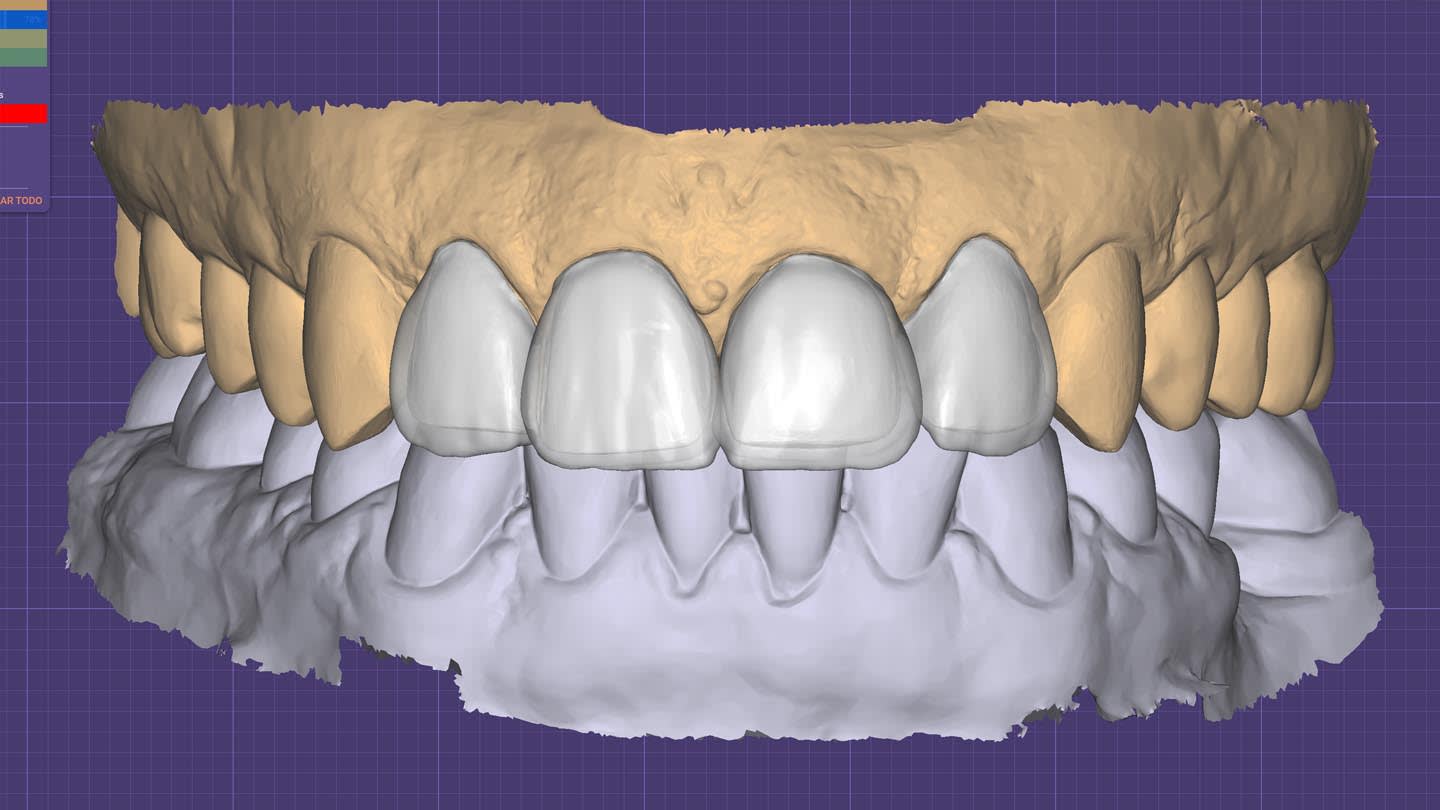

After crown removal on tooth No. 9, recontouring, and polishing, and veneer preparations of teeth Nos. 7, 8, and 10, the patient’s upper and lower arches were digitally scanned (TRIOS 4, 3Shape). These scans, along with digital photographs, were uploaded and integrated into the software (Digital Smile System SRL, digitalsmiledesign.com) for the virtual planning of the four veneers on teeth Nos. 7 through 10 and the opaque-core crown for No. 9 (Figure 4 through Figure 6). Ceramics with medium or high opacity, intended for the fabrication of core structures, were appropriate for this case. A lithium disilicate–reinforced monochromatic ceramic block with high-opacity color for CAD/CAM technology (IPS e.max®, Ivoclar, ivoclar.com) was used to fabricate the core for tooth No. 9. Then, it was fired in an oven (Zubler Vario Press 300, Jensen Dental, jensendental.com) for 5 minutes at 750°C and for 10 minutes at 850°C to complete crystallization, according to the manufacturer’s recommendations.

The opaque-core crown was tried-in on tooth No. 9 and approved in terms of marginal fit, preparation adaptation, and shade matching with the adjacent incisors. After this assessment, the crown was prepared, similar to the remaining teeth, to receive a ceramic veneer. A new digital intraoral final impression (TRIOS 4) was made for all four maxillary incisors, and the standard tessellation language (STL) files were sent to the laboratory for the manufacture of lithium-disilicate porcelain veneers (IPS e.max) using subtractive milling technology (PrograMill® PM5, Ivoclar). All data transfer from 3D planning to the laboratory CAD/CAM process is faster, easier, and more predictable than conventional methods, resulting in less manufacturing time and chairtime and enhanced final esthetic results (Figure 7 and Figure 8).16-18